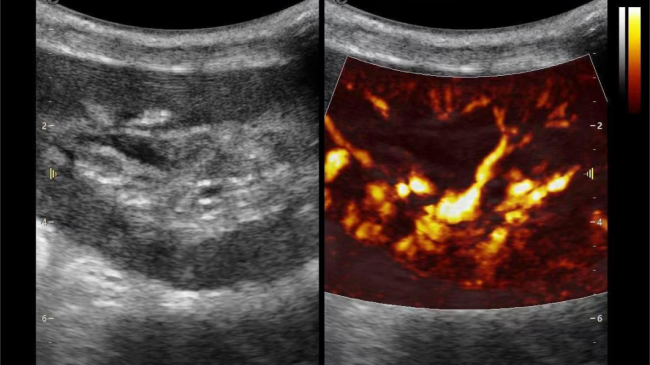

在肾移植领域,医生最怕的不是手术刀下的惊心动魄,而是那些手术后肉眼看不见的危机——急性排斥反应导致的血小板聚集形成的微血栓、毛细血管网损伤等...这些“隐形杀手”曾让无数移植肾在悄无声息中衰竭。而银河官网医疗(ESI)的iPlane Vascular平面波超微细血流显像技术,正是为破解这一难题而生。

2) 可检测20-50μm级细小血管低速血流信号,能看清头发丝1/2粗细的微血管;

微米级超高分辨率血流信号显像

超微视血流显像评估肾移植术后灌注情况